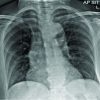

She was taken for debridement of a wound with intramedullary nailing for tibial shaft fracture (closed, Static) immediately on January 26, 2024. A prophylactic dose of injection LMWH 0.4 was given subcutaneously post-operatively after 6 h and once daily later. Triple antimicrobials were given as a prophylaxis for wound infection. She was mobilized non-weight-bearing on the right lower limb for 2 days, but on the 3rd day during physiotherapy and mobilization, she developed shortness of breath. She was evaluated clinically and her arterial blood gas analysis (ABGA)and chest X-ray were apparently normal. Her D-Dimer was found to be elevated >6.5. She was evaluated by a cardiologist and pulmonologist and investigations electrocardiogram (ECG), 2D echocardiogram (ECHO) and computed tomography pulmonary angiography (CTPA) were done. ECG was within normal parameters but 2D ECHO showed dilated right atrium (RA), and right ventricular (RV) with normal ejection fraction. CTPA showed saddle embolism at the junction of pulmonary artery division extending into B/L pulmonary arteries and into lobar, segmental arteries (Fig. 2). She was shifted to the intensive care unit (ICU) for monitoring and was decided upon two options for treating PE: First was to aspirate the thrombus with a catheter by doing an angiogram and second was to do IV thrombolysis with drugs. IV thrombolysis with injection tenecteplase 30 mg was given stat. In post-thrombolysis, there was no active bleeding or soakage from an operative wound or sutured lacerated wound. Later, she was started on an injection of LMWH 0.6 twice daily and the prothrombin time-international normalized ratio was monitored. After 2 days, the patient was shifted out from ICU and started on tab rivaroxaban 20 mg once daily.